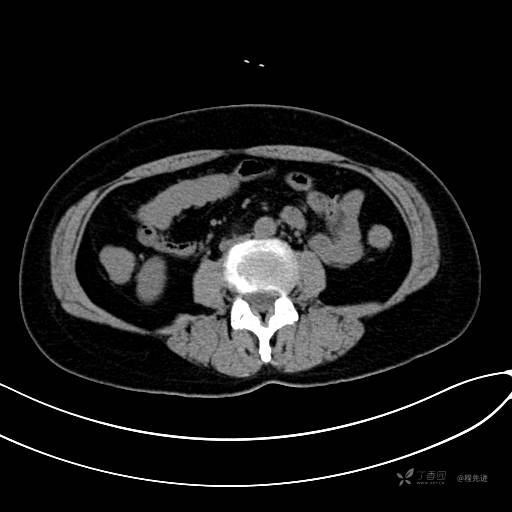

CT增强门脉期